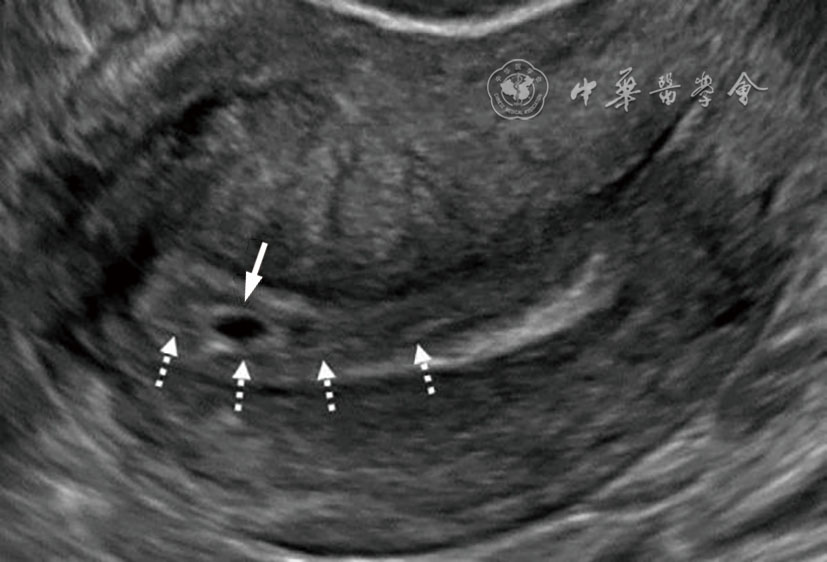

2.宫内妊娠的偏心着床(图2):指受精卵偏心着床于结构正常的子宫。正常妊娠的着床部位常靠近子宫中线,也偶可偏向左右侧,即偏心着床;此时,超声报告应提示为“宫内妊娠”或描述为“妊娠囊偏心着床但完全被子宫内膜包绕”,结论为“宫内妊娠”。该专家共识明确提出了应避免继续使用既往常用的‘宫角妊娠’‘宫角部妊娠’术语表述。

图2 宫内妊娠的偏心着床超声图像,妊娠囊位于偏心位置,但完全被子宫内膜包绕。图a为36岁孕妇(孕5周4天)经阴道超声横切面灰阶超声图,显示一偏离中线靠近左侧的妊娠囊(箭头所示)内含卵黄囊及胚胎。妊娠囊完全被子宫内膜包绕,可直接报告为“宫内妊娠”;也可补充描述为“妊娠囊偏心着床但完全被子宫内膜包绕”,但超声仍提示为“宫内妊娠”,以免与输卵管间质部异位妊娠混淆,避免使用‘宫角妊娠’或‘宫角部妊娠’等术语。图b为三维超声冠状面重建图,有助于确认妊娠囊位于子宫内膜内(图2译自参考文献[1])

考虑该专家共识对既往这一易混淆的临床问题提出明确的重新定义,是因为既往很长一段时间使用的‘宫角妊娠’,实际包含了“宫内妊娠的偏心着床”及“输卵管间质部异位妊娠”两种情况,短期超声随访或三维冠状面重建对两者的鉴别诊断较有帮助。